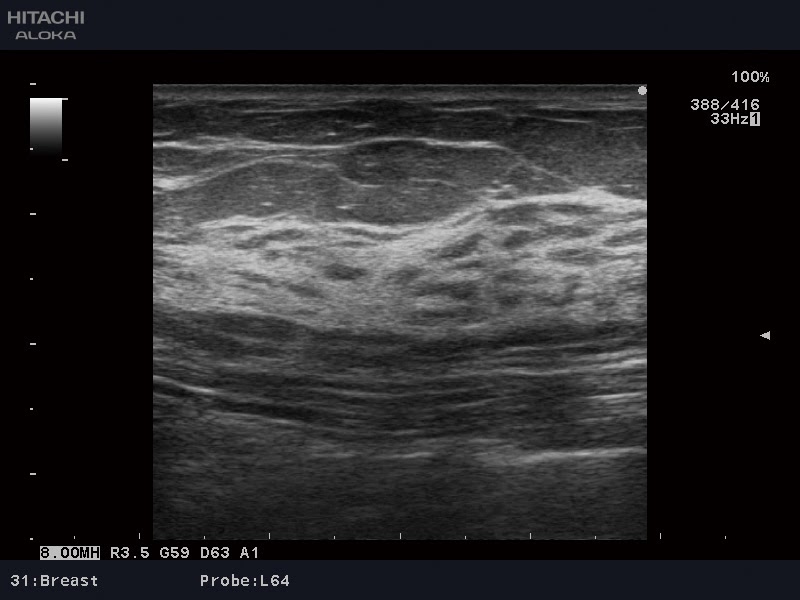

- Компрессионная эластография

Тканевый адаптивный фильтр HI Rez+

- Динамическая тканевая гармоника высокой чёткости HdTHI

- Высокое качество изображений и мощный процессор аппарата обеспечивают повышенную точность диагноза.